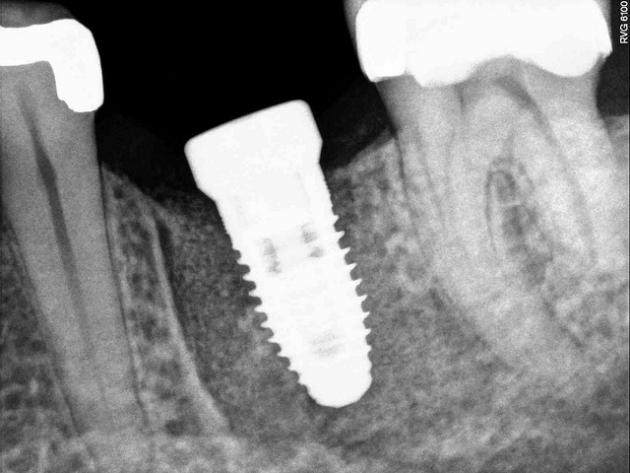

Przedstawiono w niej najważniejsze czynniki wpływające na rozwój rynku oraz obiecujące innowacje zaproponowane przez naukowców. Co liczy się dziś przy opracowywaniu powłok na implanty? Oczywiście biokompatybilność – gwarancja sprawnie przebiegających procesów gojenia i ograniczenie do minimum ryzyka odrzutu. W przypadku implantów przenoszących duże obciążenia to jednak nie wystarczy, potrzebna jest również doskonała wytrzymałość i odpowiednie właściwości mechaniczne.

Do oryginalnych, ale bardzo obiecujących pomysłów należy na przykład wykorzystanie pajęczego jedwabiu do pokrywania implantów silikonowych. Jest on hipoalergiczny i biodegradowalny, toteż świetnie sprawdza się w tej roli. Pojawiają się także propozycje powłok o dodatkowej roli terapeutycznej oraz modyfikowanych powierzchniowo, na przykład poprzez immobilizację biomolekuł, które wspomagają procesy gojenia.